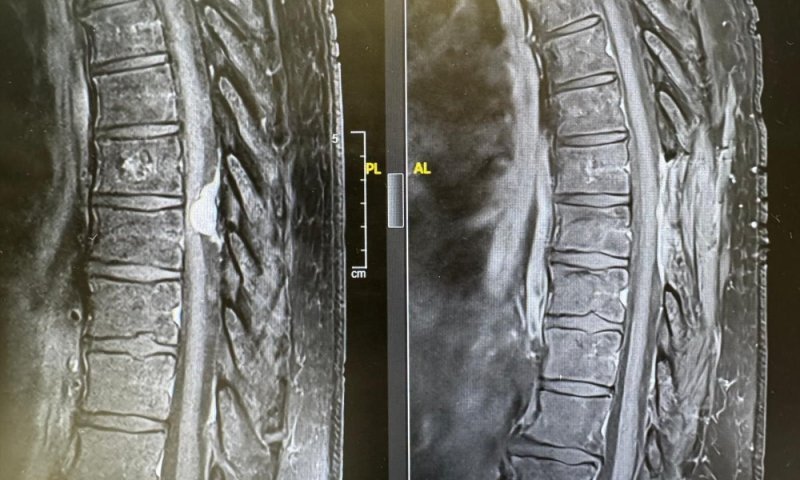

רק כשהגעתי לשערי צדק הבינו, לאחר שד"ר מרדכי לין מהמחלקה הניורולוגית עשה לי בדיקת MRI, שיש לי גידול שפיר בעמוד השדרה בגודל של כדור טניס. הגידול הוסר בניתוח ומיד לאחריו התחלתי להרגיש שיפור והצלחתי להזיז את רגל שמאל. בזכות הצוות המדהים של הרופאים והאחיות בשערי צדק, אני מצליחה לעשות היום משהו שלא יכולתי בעבר. מעולם לא קיבלתי יחס כזה מצוות רפואי - הם פשוט מלאכים, אין לי מילה אחרת, לא רציתי לעזוב את בית החולים מרוב שהחוויה הייתה טובה".

מניגיומה של עמוד השדרה הוא גידול שפיר שנמצא בתוך הקרומים של עמוד השדרה. הגידול, שנפוץ בעיקר בקרב נשים בגילים מבוגרים יותר, גורם ללחץ על עמוד השדרה ועל העצבים ומוביל לתסמינים שונים בידיים וברגליים, ובהם, נימול, חולשה בגפיים, בעיות בהליכה ואף לשיתוק.